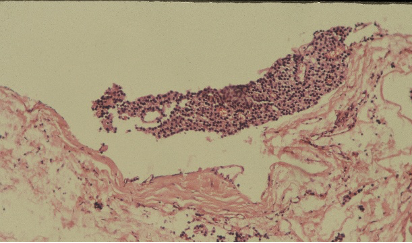

Ans to previous : (August 2025)

Tumour embolus in a lymphatic channel.